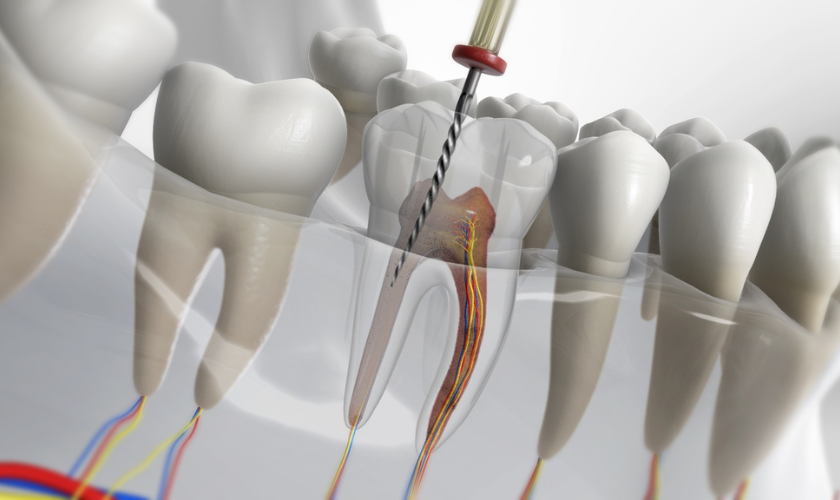

A root canal is a dental procedure used to treat infection or damage inside a tooth. The pulp, which contains nerves and blood vessels, is removed, and the inside of the tooth is cleaned, disinfected, and sealed. This treatment prevents further infection and saves the tooth from extraction.

The dentist carefully drills into the tooth and removes the infected tissue. This is done with either hand files or rotary tools.

The canals are cleaned and disinfected thoroughly. In advanced treatments, lasers or ultrasonic tools are used for better results.

The cleaned canals are filled with gutta-percha, a biocompatible material. The tooth is then sealed to prevent future infection.